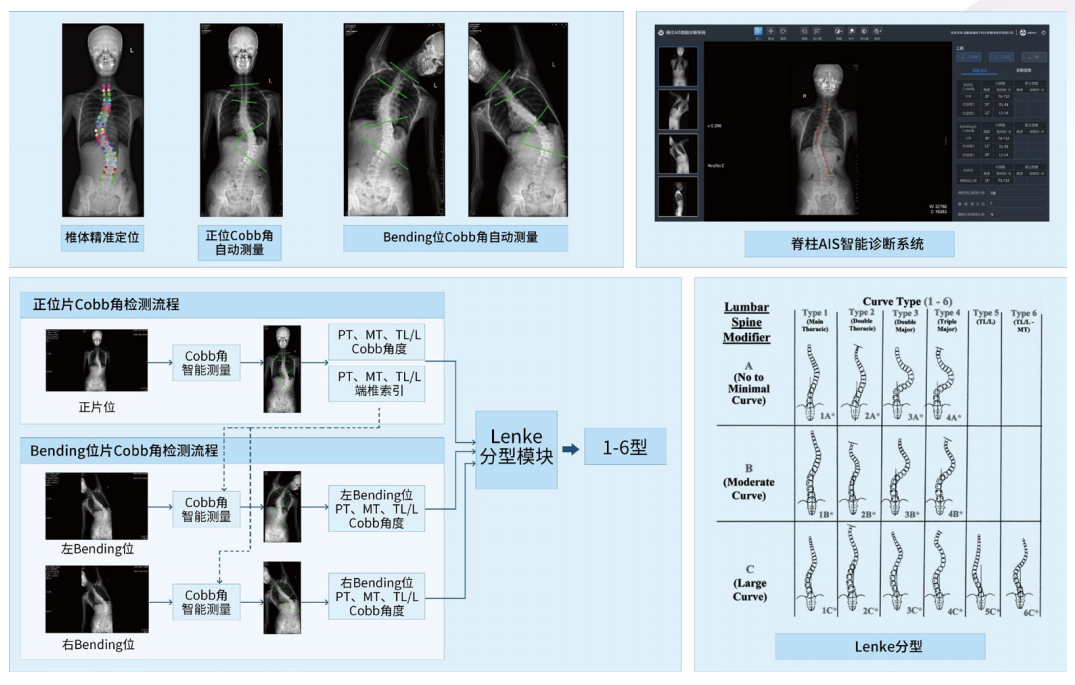

利用人工智能深度神经网络结合医学影像处理技术,智能提取背部C7、肩胛骨下角、腰窝及骶骨六个姿态关键点,智能评估冠状面Cobb角度,实现脊柱侧弯快速筛查。

1.完善的测量系统:符合临床X光脊柱全长片阅片流程的AI测量系统。

2.高效率:产品读片+测量+诊断一共是3-5秒/病人,比医生的15分钟读片时间提速300倍。

3.高稳定:大样本测试下,cobb角测量误差与医生相当(5度以内)。